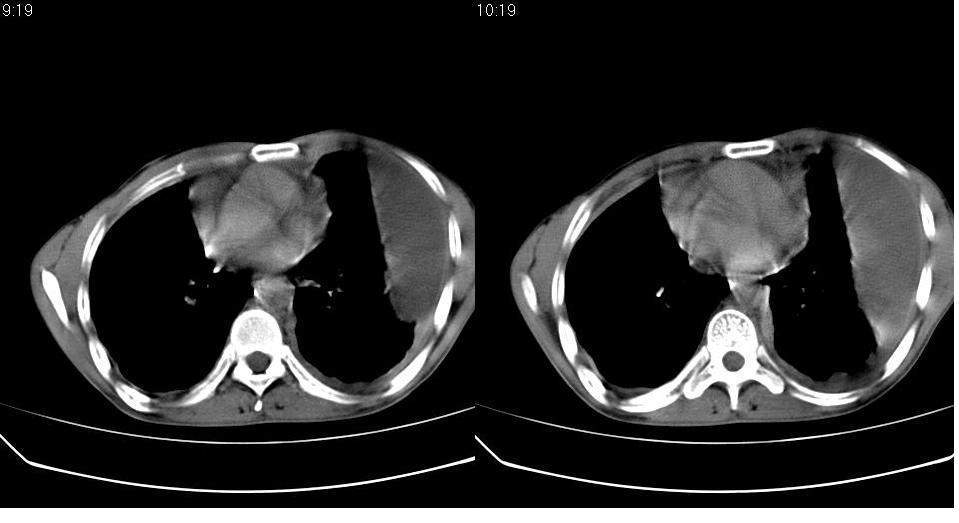

以下是引用苯小孩在2007-6-27 15:09:00的发言:[br]考虑:1、右肺继发性肺结核.2、双侧包裹性积液<胸腔及叶间>3、双侧局部胸膜增厚.[br]建议胸水化验检查.

以下是引用yanghaochen88在2007-6-27 15:08:00的发言:[br]双肺上野散在粟粒状影、包裹性积液、胸膜增厚粘连、叶间积液---tb,至于分型还得结合病史体征细究妥当些。